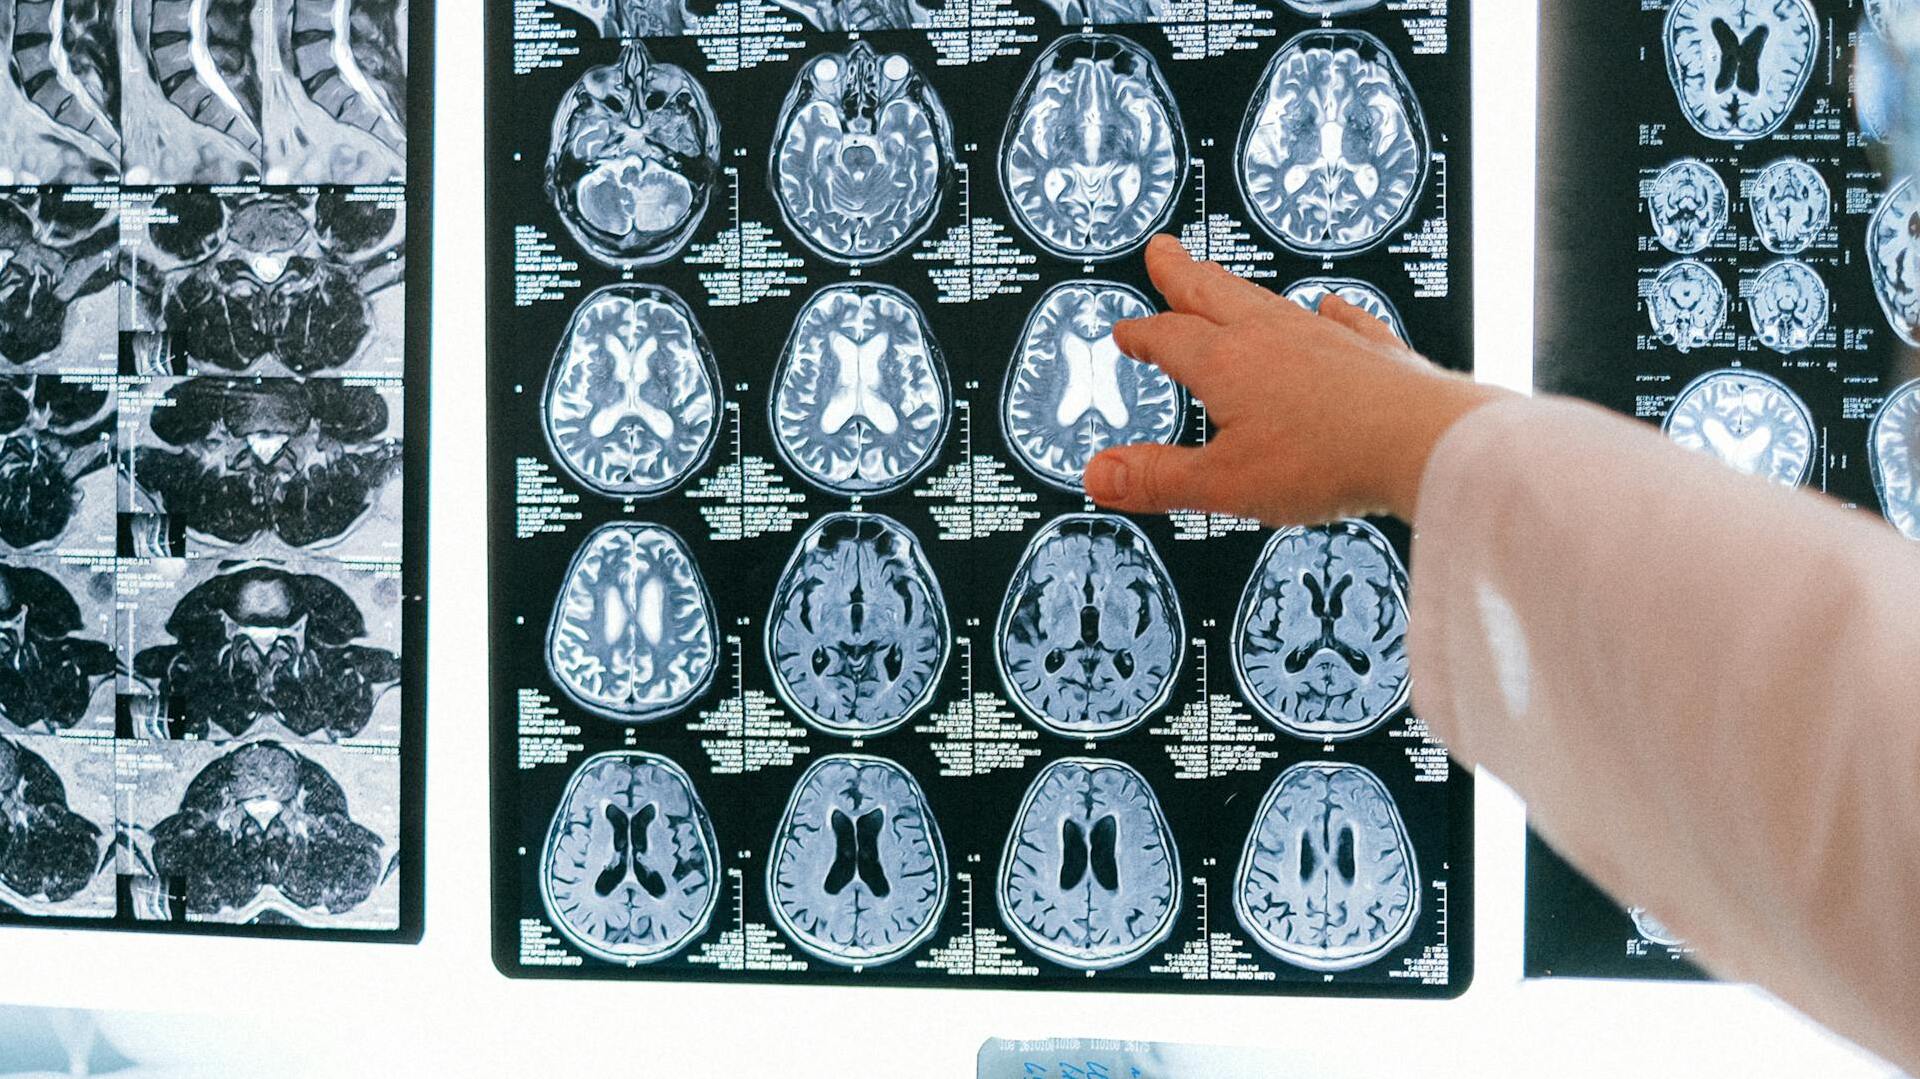

Un nuevo estudio ha mostrado ciertas diferencias en los cerebros de personas con psicopatía, especialmente en aquellos que muestran rasgos antisociales marcados. Publicado en European Archives of Psychiatry and Clinical Neuroscience, la investigación utilizó imágenes avanzadas y el Julich-Brain Atlas para examinar cómo estos rasgos se relacionan con cambios en el volumen cerebral.

Con este fin, fueron seleccionados 39 hombres con una puntuación PCL-R de 20 o más de instituciones forenses alemanas, incluidas prisiones y hospitales psiquiátricos de seguridad. Estos sujetos fueron comparados con un grupo control sin rasgos psicopáticos. Todos los participantes se sometieron a resonancias magnéticas cerebrales.

Con los resultados de las imágenes, los investigadores realizaron comparaciones entre los dos grupos utilizando el atlas Julich-Brain, que les permitió discernir las diferencias volumétricas entre las distintas regiones del cerebro. Los resultados indicaron que los individuos con puntuaciones más altas en el Factor 2 del PCL-R mostraban reducciones en el volumen cerebral de varias áreas críticas.

Estas áreas incluían los ganglios basales, el tálamo, el tronco encefálico (especialmente el puente), el cerebelo y partes del cerebro que gestionan la toma de decisiones y la conducta social, como las cortezas orbitofrontal e insular. Estas regiones ejercen un rol clave en la regulación de las emociones y el control de los impulsos, por lo que podría un menor volumen en esas zonas podría influir en el desarrollo de comportamientos antisociales.

De forma interesante, también se observó una reducción general del volumen cerebral total entre los participantes con psicopatía. El cambio localizado más significativo se encontró en una parte del hipocampo llamada subículo derecho, que es importante para la memoria. En cambio, los rasgos relacionados con el Factor 1 mostraron vínculos más débiles con la estructura cerebral y mayor variabilidad entre los individuos.